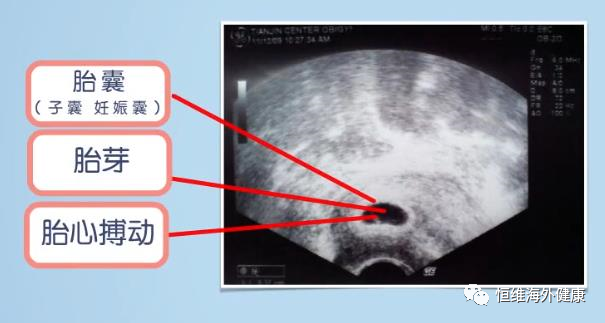

其实正常情况下,通过经阴道超声检查,在停经大约5周会看到孕囊,6~8周左右就会出现胎心、胎芽。

但如果在这些时间点都没有看到应该出现的孕囊、胎心或胎芽,就有可能是“胎停”,但是也不能轻易就给出“胎停”的诊断。